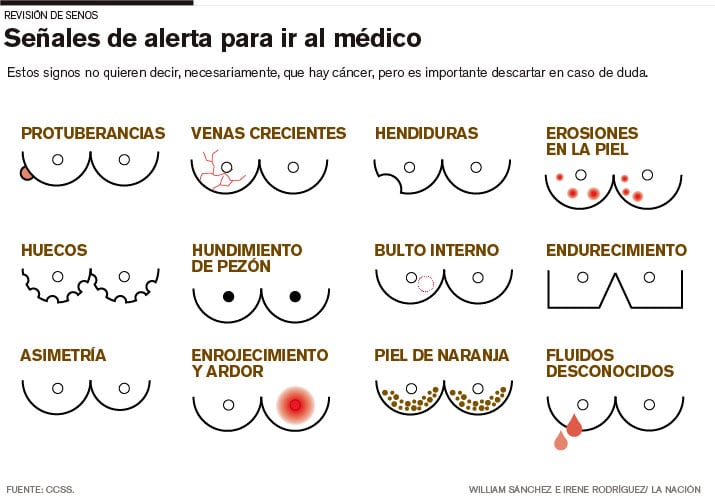

No fume. Un estudio en el British Medical Journal afirmó que el tabaquismo sube el riesgo de tumores un 16%. Autoexamen. No solo sospeche de "bolitas" en los senos; en muchos casos, esas pelotitas están formadas simplemente por grasa.

Los tumores pueden dar otro tipo de señales, como protuberancias, venas crecientes, hendiduras, erosiones en la piel, huecos, hundimiento en el pezón, fluidos desconocidos, endurecimiento, "piel de naranja", o enrojecimiento y ardor. Mamografía. Lo ideal es hacerse una cada dos años después de los 50 años, pero si tiene familiares con este mal, debe comenzar desde más joven.